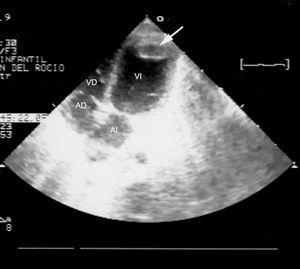

Fue tratado mediante ventilación mecánica, diuréticos e inotrópicos (dopamina, dobutamina y noradrenalina), y se añadió heparina tres días después, por aparición de un trombo apical en el ventrículo izquierdo (fig. 2), con lo que el paciente permanecía en situación crítica.

Figura 2. Trombo en el ápex del ventrículo izquierdo (13 días de vida): ecocardiografía 2D, proyección apical 4C. El trombo alojado en la región apical del ventrículo izquierdo tiene un diámetro de 1 cm.